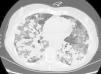

Presentamos el caso de una mujer de 57 años, exfumadora, y con antecedentes de adenopatías cervicales y axilares no patológicas, mastitis granulomatosa no necrosante y mielopatía dorsal aguda. La paciente fue hospitalizada por bronconeumonía y se le realizó una broncoscopia con biopsias transbronquiales que resultaron anodinas, y lavado broncoalveolar (LBA) en el que se observó un 65% de linfocitos y un cociente CD4/CD8 normal. La paciente reingresó por presentar un derrame pleural derecho, que se etiquetó de exudado linfocitario sin celularidad maligna, hepatoesplenomegalia y signos de hipertensión pulmonar. En el estudio destacó un déficit de las subclases de IgG. Se inició tratamiento con prednisona. Posteriormente, la paciente presentó disnea y síndrome constitucional. La tomografía computarizada torácica objetivó nódulos pulmonares peribronquiales de bordes imprecisos, con broncograma aéreo y tendencia a coalescer formando grandes masas en los lóbulos inferiores. Estas masas estaban rodeadas de áreas en vidrio esmerilado y adenopatías mediastínicas, hallazgos compatibles con granulomatosis linfomatoide, si bien las áreas en vidrio esmerilado y las adenopatías no son típicas de la granulomatosis linfomatoide y podrían estar relacionadas con el hábito tabáquico (fig. 1). Las pruebas funcionales mostraron una restricción moderada, con difusión del 36%, y en la analítica destacó una leucopenia debida a linfopenia. Se realizó biopsia de médula ósea y una segunda broncoscopia, cuyo LBA mostró un predominio linfocitario y un cociente CD4/CD8 normal. La punción de una adenopatía paratraqueal derecha no aportó más información. Los cultivos y la citología fueron negativos. Se practicó una biopsia pulmonar, tras la cual, la paciente sufrió un empeoramiento clínico-radiológico.